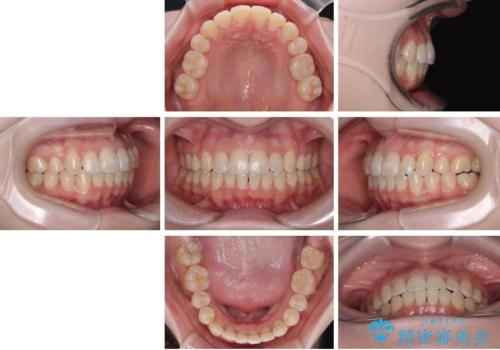

八重歯が気になる。補助装置を併用したワイヤー矯正

補助装置を併用したおかげで、出っ歯になることなくスムーズに治療を終えることができました。